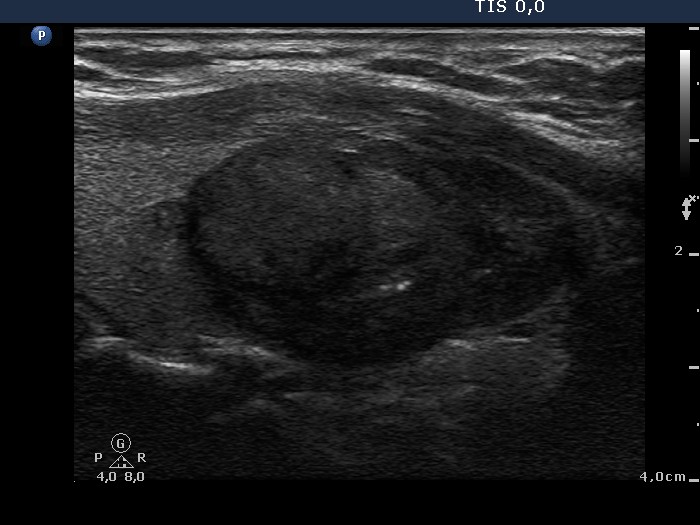

Ultrasonography: the thyroids were echonormal. There was an echonormal nodule occupying almost the entire right lobe. The lesion displayed a halo sign, cystic degeneration and presented perinodular blood flow.

5 sessions of sclerotherapy were performed. We demonstrate the 1st and 4th session.